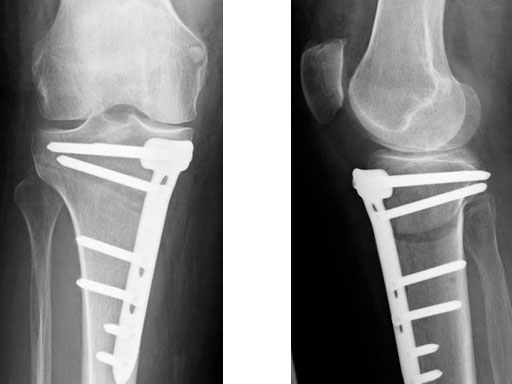

A 68-year-old female.

Case provided by Alex Staubli, Luzern, CH

The correction is planned on a long-leg standing x-ray. After surgery, the mechanical axis should pass through a point 63% on the lateral side of the total width of the tibial plateau in the frontal plane. A transverse or slightly oblique incision is used to avoid damage to the saphenous nerve. The distal fibers of the medial collateral ligament are detached from the tibia. Under fluoroscopic control, two wires are placed in the proximal tibia marking the transverse osteotomy plane. The cut usually starts at the upper margin of the pes anserinus and ends at the tip of the fibula on the lateral side. The wires are placed exactly parallel to the tibial plateau thus taking into consideration the individual tibial slope of the patient. An incomplete cut of the posterior two-thirds of the proximal tibia is performed with an oscillating saw guided by the wires. Continuous irrigation avoids burn injury to the bone. A second osteotomy is now performed in the anterior third of the tibia in an angle of 100 ending above the patellar tendon insertion. A smaller saw blade is used and the complete anterior cortex is cut exactly in the frontal plane. The osteotomy is now gradually opened by inserting flat chisels or a spreader-chisel into the posterior osteotomy cleft. This process may take some minutes and can usually be completed without fracture of the lateral cortex. A bone spreader is now placed in the posteromedial edge of the tibia and the chisels are removed. The leg is extended and the correction is checked with the fluoroscope. A long metal rod is placed between center of the hip joint and center of the ankle joint. The projection of this rod should be at the planned point of correction on the tibial plateau lateral of the midline. Eccentric collapse of the medial joint space may cause accidental overcorrection. In this case pressure on the foot may simulate loading and body weight. The correction can be fine-tuned by opening or closing the spreader. The TomoFix Medial Tibia Plate is now placed in a subcutaneous pocket. The implant is precontoured and usually fits well to the bone surface. The distance holders avoid compression of the medial collateral ligament and the pes anserinus. Three proximal bolts are placed near the subchondral sclerosis zone. The position of the bolts is adapted to the anatomy of the proximal tibia giving optimum purchase for the bolts. An oblique lag screw is inserted distal to the osteotomy. This screw in the first combination hole allows careful compression of the lateral osteotomy hinge and pretensioning of the implant. A stab incision is created on the shaft and the implant is fixed monocortically with bolts. The lag screw and the distance holders are replaced by bolts. The medial collateral ligament is released longitudinally to reduce medial compartment pressure and the wound is closed in layers. An overflow drain may be used. Clinical and experimental work has proven that when this technique is closely followed, corrections up to and over 15 mm can be performed without bone grafting or use of bone substitutes.

The patient is mobilized on crutches on day one after surgery. Partial weight bearing is allowed from the beginning. Biomechanical and RSA studies have proven that postoperative loading of the implant by body weight in standard partial weight bearing and early full weightbearing conditions did not cause loss of correction. Our group now allows the patients to walk without crutches as soon as the postoperative pain allows after this type of surgery. Members of the Knee Expert Group (KNEG) have presently implanted over 1,500 TomoFix medial tibia. The results are extremely positive in respect to osteotomy healing, implant failure, and surgical complications.